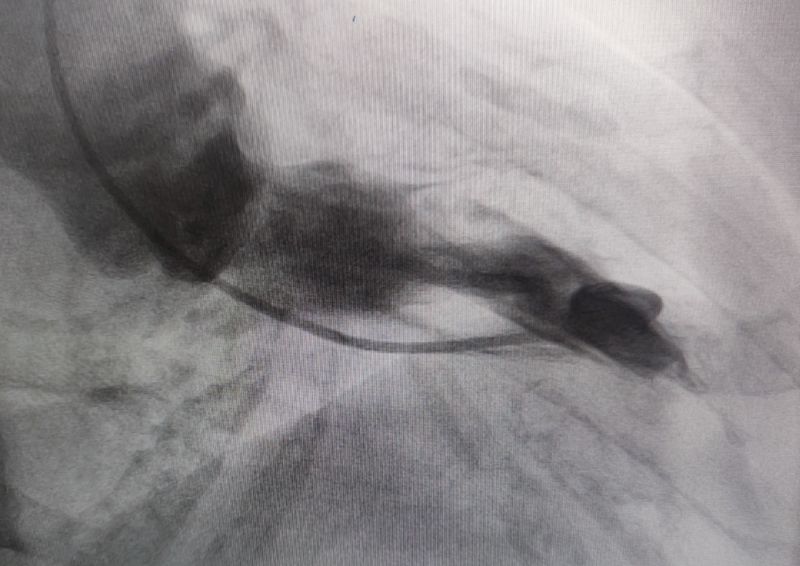

左室造影(左心室收縮期)

72歲的王女士(化名),早在7年前就被心臟彩超確診為室間隔肥厚并流出道梗阻。近期,她因“反復(fù)胸悶、氣短20余年,加重伴惡心、嘔吐1周”入住消化內(nèi)科。入院復(fù)查心臟彩超結(jié)果顯示:EF值為62%,F(xiàn)S值為34%;室間隔中上段厚度達(dá)到18.5/17.7毫米,左室流出道最大血流速度高達(dá)547cm/s,PG值為119mmHg,明確診斷為梗阻型肥厚型心肌病。同時(shí),腦鈉肽檢測(cè)值為3050.6ng/l。綜合評(píng)估后,王女士轉(zhuǎn)入心血管內(nèi)科九病區(qū)接受進(jìn)一步治療。